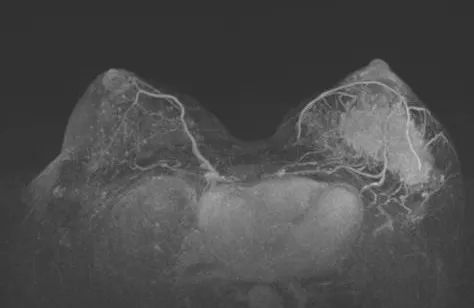

2021-11 乳腺MRI:左乳上份、外上象限见一不规则等T1,等-稍长T2信号肿块,大小约8.2cm×3.7cm×6.5cm,ADC值最低处0.71×10E-3mm2/s,动态增强扫描不均匀显著强化。左腋下多枚肿大淋巴结,大者约2.2cm×1.3cm,增强明显不均匀强化。形状呈不规则,边界欠清楚。

图2. 新辅助治疗前乳腺MRI

图7. 上图为治疗前,下图为治疗6周期后

治疗6个周期后,乳腺增强MRI显示靶病灶明显缩小,临床疗效评估为PR;腋窝靶病灶消失,临床疗效评估为CR。